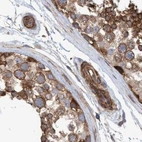

Immunohistochemical staining of human colon, endometrium, liver and testis using Anti-SPECC1 antibody HPA021421 (A) shows similar protein distribution across tissues to independent antibody HPA021430 (B).